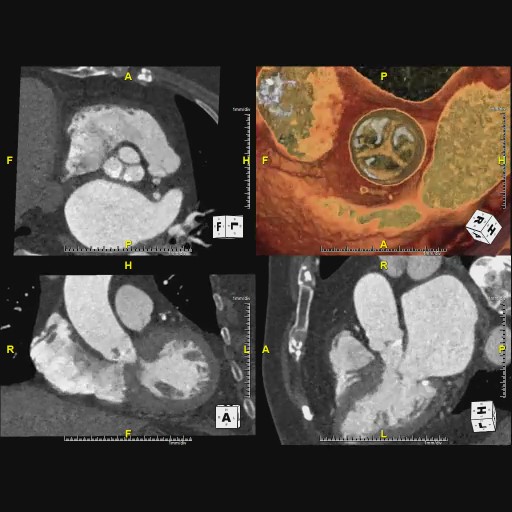

心臓弁膜症に対する治療法として、薬で症状を緩和し経過観察を行う保存的治療、開胸手術で心臓の弁の修復や交換を行う外科的治療、開胸せずに心臓を止めることなく、カテーテルを用いて弁を植え込むカテーテル治療という3つの治療法が選択肢となります。放射線科では、弁やその周囲の石灰化、血液循環の状態を調べて治療方法を決定するための重要な情報を提供します。また、弁の手術後の経過なども調べることができます。

経カテーテル大動脈弁植込み術(TAVI)施行前と後